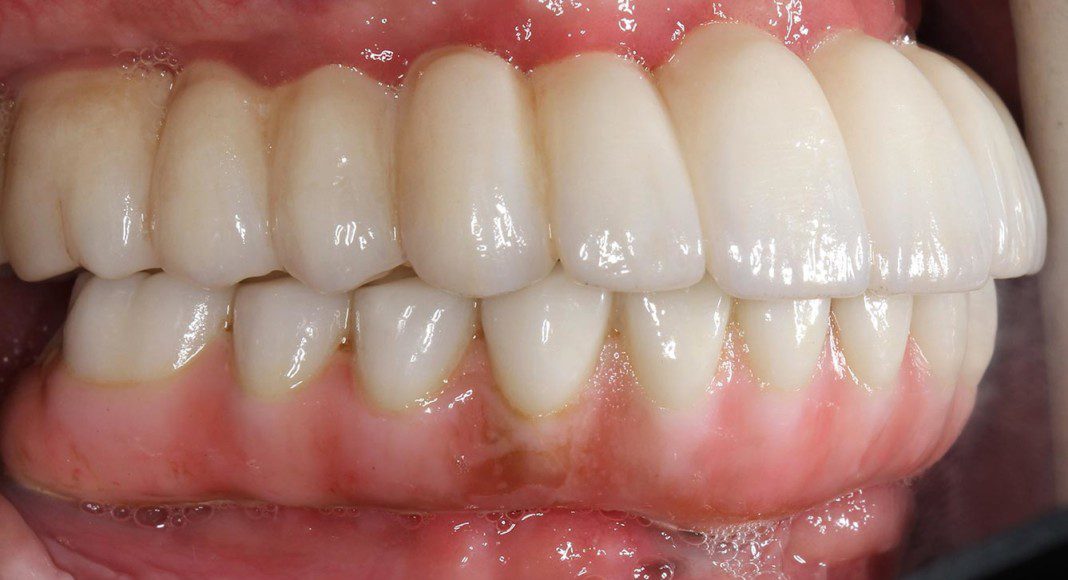

After two months of implant healing, the remaining teeth are removed, additional implants placed and the temporary bridges modified or new ones are fabricated. See next picture.

New upper and lower temporaries are fabricated and are retained by only the implants as there are no natural teeth remaining.